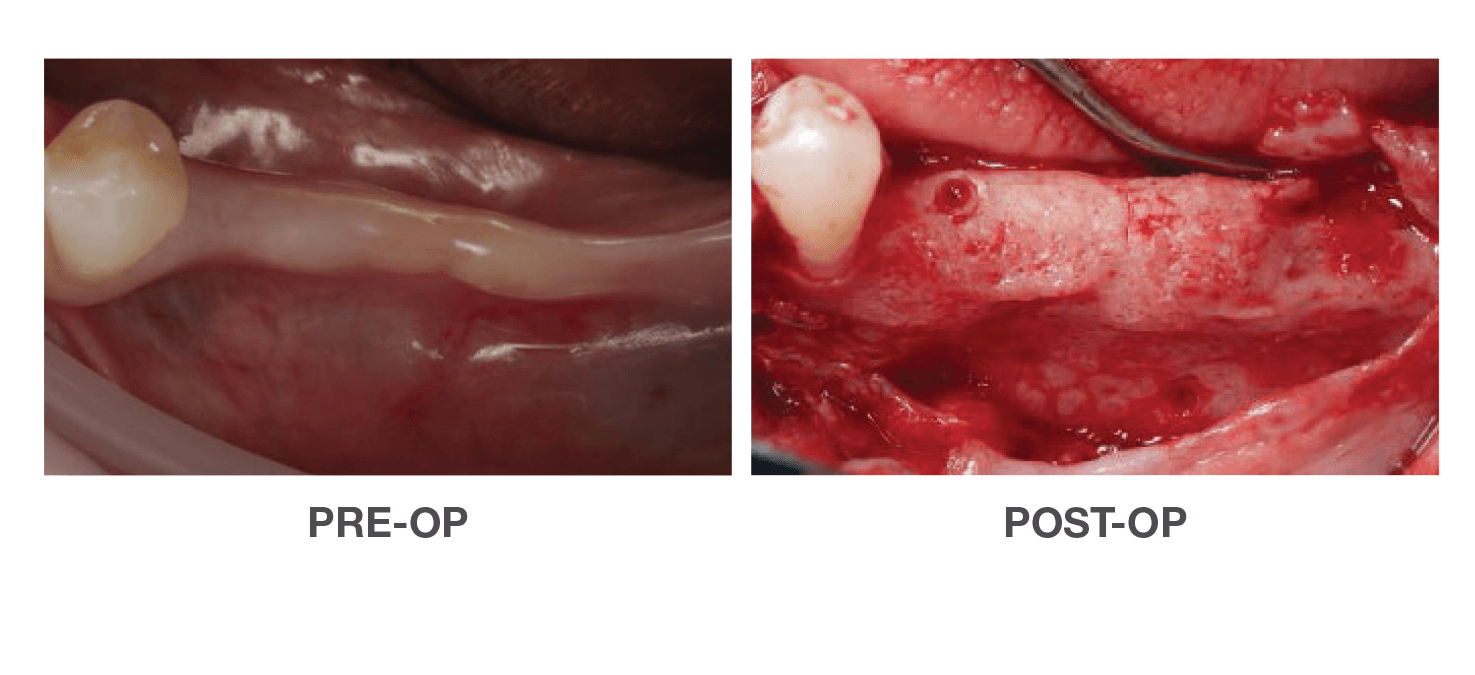

Vertical Ridge Achievement

Using OraGen® Cellular Bone Matrix

Case performed by: Dr. Edgard El Chaar, New York, NY

Horizontal Ridge Achievement

Using OraGen® Cellular Bone Matrix

Case performed by: Dr. Edgard El Chaar, New York, NY

Successful Vertical & Horizontal

Augmentation to Repair Failed Implant

Using OraGen® Cellular Bone Matrix

Case performed by: Dr. Robert Miller, Plantation FL